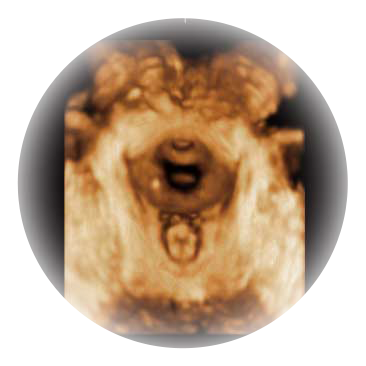

可同时显示组织结构表面和内部的轮廓信息,达到透视效果,为临床提供更丰富的诊断信息。

宽频带腹部凸阵探头和腹部容积探头、大角度腔内探头和腔内容积探头、独特的生殖专用曲柄探头,为妇产应用提供全面诊疗方案。

大角度腔内容积探头,可完整包络子宫及盆底结构,充分展示组织结构毗邻关系。